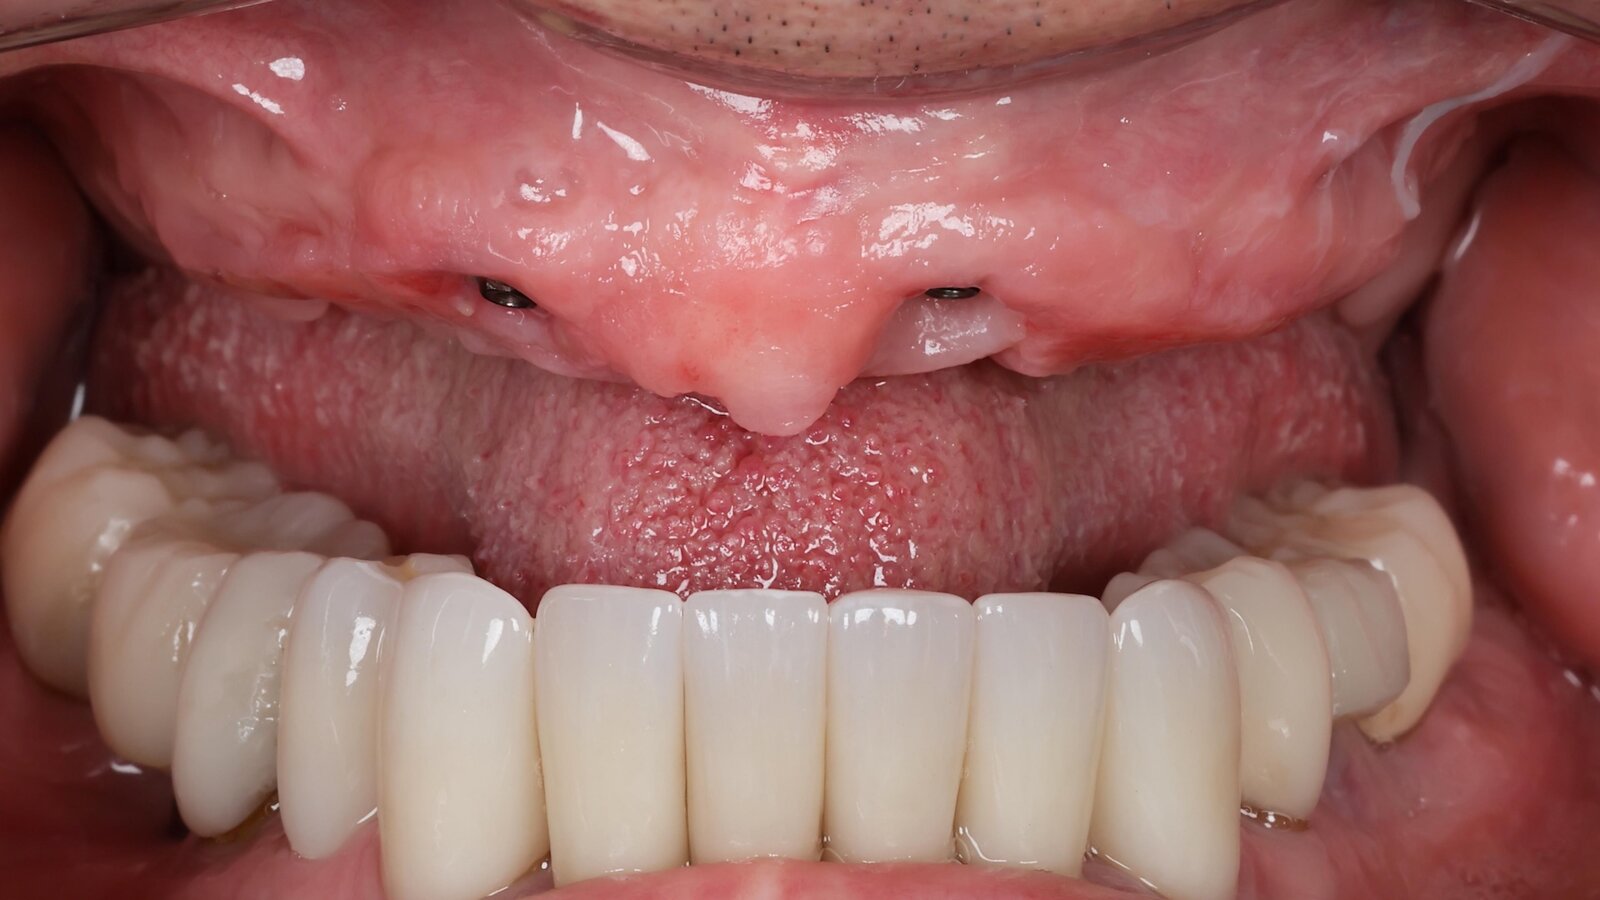

Figura 3. Impresión digital captada por fotogrametría en la que se observa la digitalización de múltiples implantes y su posición espacial. Foto: Marinelly Mendes

Figura 4. La transferencia postquirúrgica de la posición de los implantes es una de las características más relevantes de la fotogrametría. Foto: Marinelly Mendes

La odontología digital ha transformado el diagnóstico, la planificación de la rehabilitación y la fabricación protésica. En implantología oral, la transferencia fiel de la posición tridimensional de los implantes es crítica para lograr ajuste pasivo y evitar tensiones protésicas que comprometan su longevidad. Aunque los escáneres intraorales (IOS) y la tomografía CBCT son ampliamente utilizados, presentan limitaciones: los IOS pueden acumular error en arcos extensos y el CBCT, aun siendo esencial para evaluar anatomía ósea, sufre artefactos por metal (1-3). La fotogrametría puede preservar relaciones espaciales relativas entre múltiples implantes en arcos completos edéntulos cuando se emplean los protocolos y scanbodies apropiados (dispositivos que se acoplan a los componentes protésicos o análogos correspondientes para referenciar tridimensionalmente sus posiciones durante un escaneo) (4-6).

La fotogrametría identifica homologías en múltiples imágenes y emplea triangulación geométrica y ajuste de grupos de estructuras (bundle adjustment) para estimar la posición 3D de puntos en el espacio. Esto produce una nube de puntos densa que se transforma en malla tridimensional texturizada, exportable en formatos estándar (STL, PLY, OBJ) para su uso en CAD/CAM o en archivos para CBCT (7,8). En la clínica, se usan frecuentemente scanbodies o marcadores con geometría definida para facilitar la alineación (matching) y generar la reconstrucción (9).

Mientras los escáneres intraorales reconstruyen superficies mediante barrido secuencial (luz estructurada, triangulación, confocalidad), la fotogrametría basa su reconstrucción en correspondencias globales entre imágenes, lo que reduce el error acumulativo típico de la posición espacial de los implantes en arcos largos. El CBCT aporta información volumétrica ósea imprescindible para la planificación, pero no ofrece la resolución superficial necesaria para la adaptación protésica; la integración multimodal (fotogrametría + CBCT) permite vincular con precisión la interfaz protésica con la anatomía ósea (1,3,10).